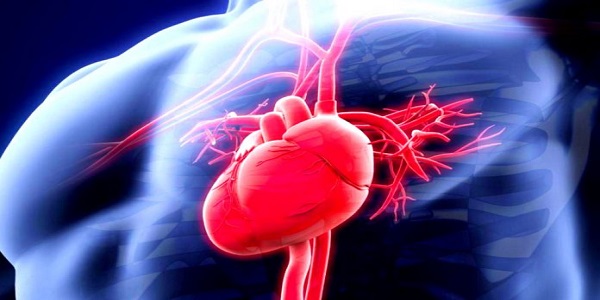

Πόσες φορές την ημέρα χτυπάει η καρδιά μας;

Η καρδιά μας είναι ένας μυς που εργάζεται ακατάπαυστα σε όλη τη διάρκεια της ζωής μας, χωρίς εμείς να καταβάλλουμε κάποια προσπάθεια. Κινείται δηλαδή ανεξάρτητα από τη θέλησή μας. Ακριβώς γι΄ αυτό είναι ένας πολύ ιδιαίτερος τύπος μυός – με αξιοθαύμαστες λειτουργίες.

Μια ισχυρή μυϊκή αντλία

Στην ουσία η καρδιά μας είναι μια ισχυρή μυϊκή αντλία, που εξασφαλίζει την κυκλοφορία του αίματος στον οργανισμό: Παίρνει το αίμα από τις φλέβες, στις οποίες βρίσκεται σε χαμηλή πίεση και το στέλνει στις αρτηρίες με υψηλή, ώστε μέσω αυτών να φτάσει σε όλα τα όργανα του σώματος.

Αποτελείται από τέσσερις μυώδεις κοιλότητες, δύο πάνω με λεπτά τοιχώματα που ονομάζονται κόλποι και δύο κάτω με παχύτερα τοιχώματα που ονομάζονται κοιλίες.

Ο δεξιός κόλπος δέχεται το αίμα από όλα τα μέρη του σώματος μέσω των μεγάλων φλεβών, το προωθεί στη δεξιά κοιλία και από εκεί στην πνευμονική κυκλοφορία με στόχο την οξυγόνωσή του. Στη συνέχεια, το πλούσιο σε οξυγόνο αίμα προωθείται από τους πνεύμονες στον αριστερό κόλπο και από εκεί στην αριστερή κοιλία. Η τελευταία αποτελεί το πιο «δυνατό» και σημαντικό τμήμα του μυοκαρδίου γιατί με τη συστολή της προωθεί το οξυγονωμένο πλέον αίμα σε όλο το σώμα, μέσω της αορτής και των μεγάλων αρτηριών.

Στην καρδιά υπάρχουν επίσης τέσσερις βαλβίδες, που χρησιμεύουν στο να επιτρέπουν τη δίοδο του αίματος προς μία μόνο κατεύθυνση και να εμποδίζουν την παλινδρόμησή του κατά τη διάρκεια της καρδιακής συστολής.

Χιλιάδες χτύποι κάθε μέρα

Η μέση καρδιακή συχνότητα σε έναν υγιή άνθρωπο που δεν γυμνάζεται είναι περίπου 75 σφύξεις ανά λεπτό. Έτσι η καρδιά χτυπά περίπου 108.000 φορές την ημέρα και περίπου 40.000.000 φορές τον χρόνο!

Ο χτύπος της καρδιάς είναι ο ήχος που παράγουν οι βαλβίδες, όταν κλείνουν.